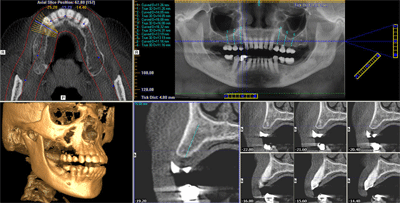

I-CAT Vision

I-CAT Vision é um software que gera imagens, onde integram módulos de visualização para ATM, implante e todos os cortes axiais, coronais e sagitais.